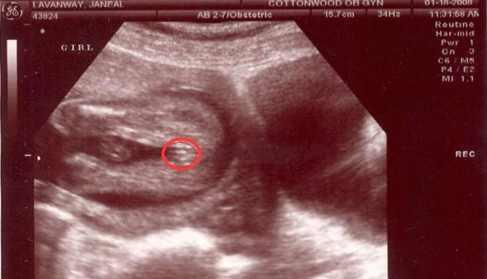

彩超图片怎么看男女,b超图怎么看男女

彩超看男女

彩超看男女三条线图片

彩超图片看胎儿性别

彩超男女性别区别图